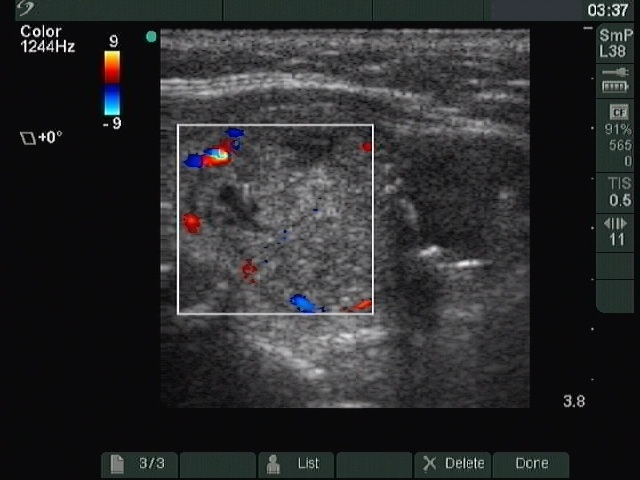

Left lobe, longitudinal scan, color Doppler mode. The lesion presents signs of perinodular blood flow.